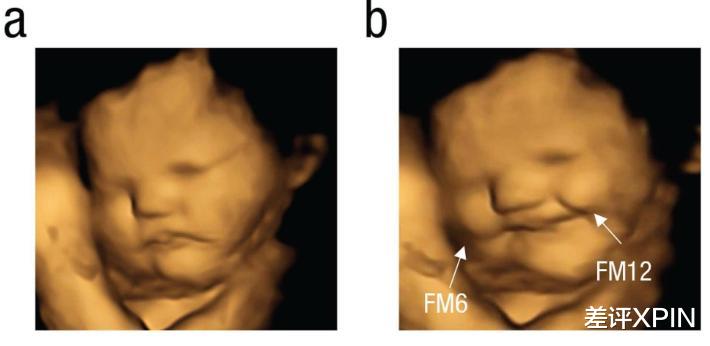

他们利用 4D 超声技术,捕获到胎儿的实时表情,严谨地证明了:原来我们自打在娘胎里就不想吃苦!!!

这张图片里可以明显看到,左边的胎儿愁眉苦脸、右边的却在眉开眼笑。是因为右边胎儿的母亲吃的是甜甜的胡萝卜粉,而左边吃到的是苦苦的羽衣甘蓝。

看来,羽衣甘蓝这破玩意连胎儿都觉得难吃。